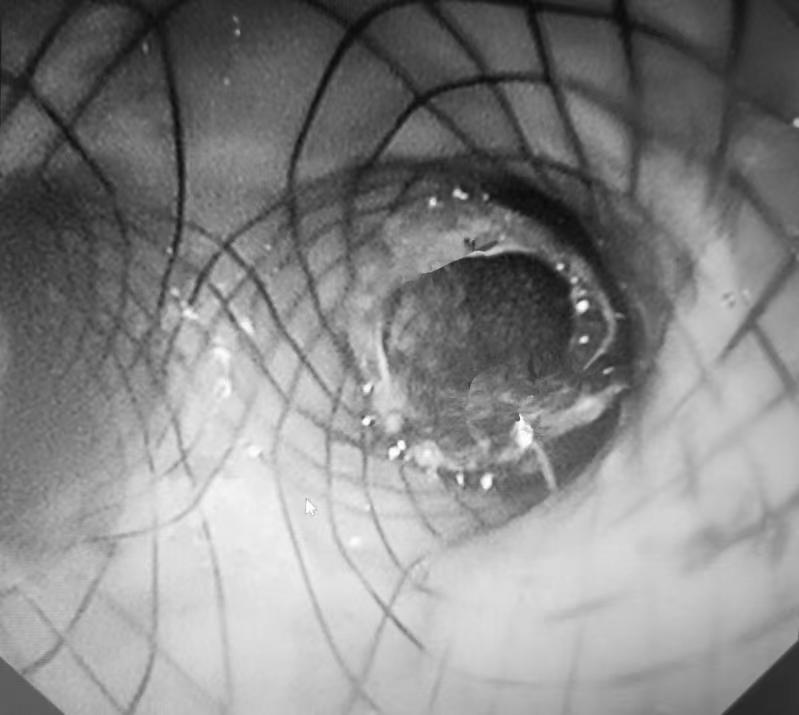

靖秋生说,饭粒窜入气管,已经引发肺上感染。必须立即将瘘口封堵。不过,瘘口所处的位置形如一个倒立的“Y”。需要通过气管镜送入一个Y形覆膜支架,通过支架上的覆膜,将瘘口堵上。

Y型气管支架的安放是呼吸内镜操作中难度极高的一项,必须一次性成功,否则会给患者带来较大痛苦,并增加操作风险。好在,凭借30多年的内镜操作经验,靖秋生只用了六七分钟就顺利将支架安放到位。

支架精准卡位,靖秋生看着气管镜传来的画面,像欣赏一件艺术品一样津津有味。他说:“医生精准安放支架,就像雕刻师精准雕刻出一件满意的作品一样,越看越有成就感。”

图三、Y型覆膜支架精准卡位后将气管、食管瘘口封住。